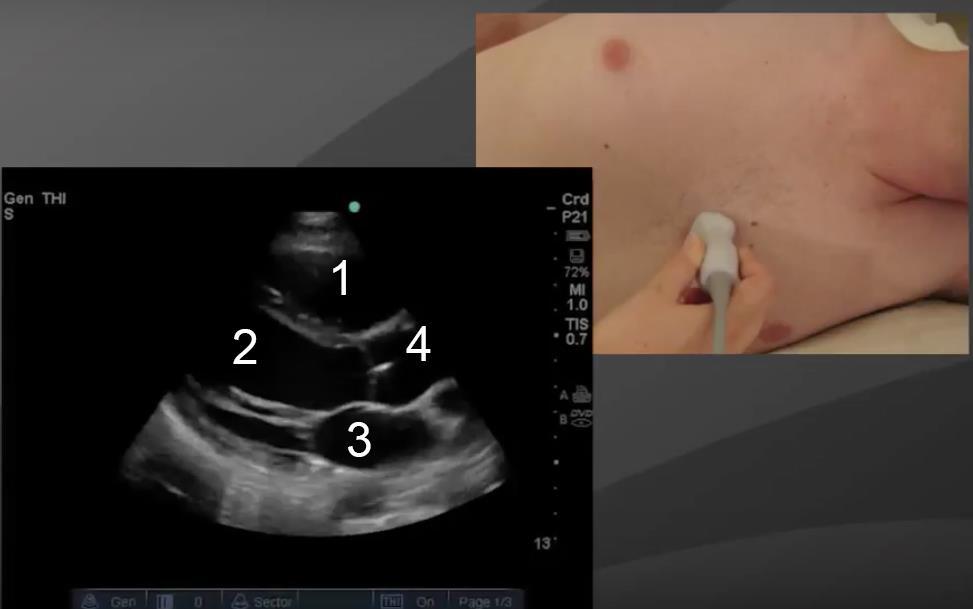

Image : Cœur : Coupe parasternale grand axe (PLAX) 1

1. Ventricule droit

2. Ventricule gauche

3. Aorte

4. Atrium gauche